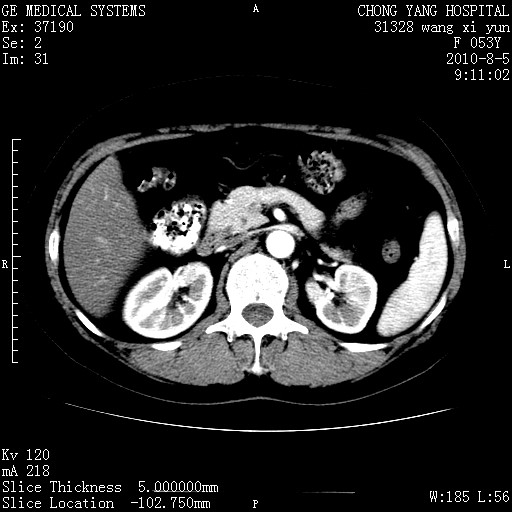

标题: CT28214:F41Y 血尿二十天,建议盆腔平扫加增强。

1)考虑肝左叶胆管细胞癌。2)脂肪肝。